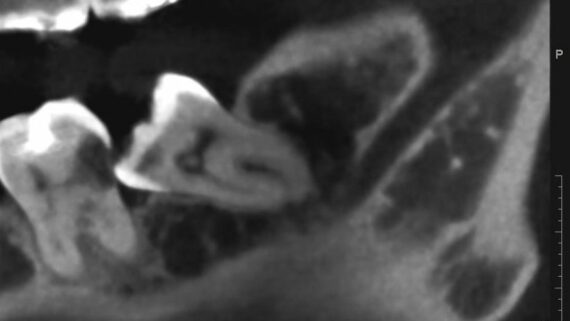

Между тем, эта остеопластика, хоть и считается одной из самых сложных имплантологических операций, для пациента очень даже комфортна и совершенно безопасна. С современными методами, инструментами и материалами, риски осложнений при подобных операциях удается удерживать на уровне 1-2%, что, согласитесь, очень круто (для сравнения, осложнения при лечении кариеса составляют немногим более 10%).

С той же остеопластикой — чаще всего ее проводят из-за выраженной атрофии костной ткани, которая вызвана длительным отсутствуем зубов. Если бы пациенту вовремя (в идеале — сразу) поставили импланты и провели протезирование — остеопластики удалось бы избежать. А, если вовремя заняться лечением зубов — возможно, был бы шанс избежать их удаления и последующей имплантации. - Не экономьте на квалификации и опыте врача. Ищите компетентного специалиста, применительно к Вашему случаю.